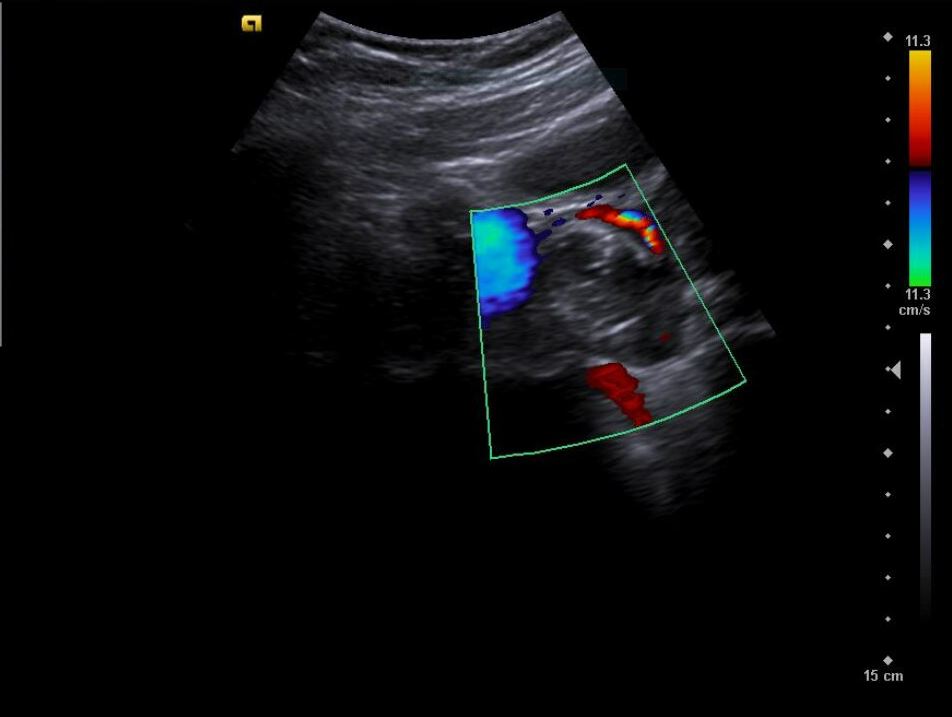

Descripción de los hallazgos ecográficos y las imágenes más relevantes para la resolución del caso

Diagnóstico inicial: Teratoma ovárico derecho versus cuerpo lúteo hemorrágico.

La paciente es valorada en consulta presencial de ginecología. Ecografía vaginal confirma: